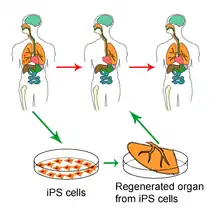

Induced pluripotent stem cells

The iPS cell technology was pioneered by Shinya Yamanaka's lab in Kyoto, Japan, who showed in 2006 that the introduction of four specific genes encoding transcription factors could convert adult cells into pluripotent stem cells.[72] He was awarded the 2012 Nobel Prize along with Sir John Gurdon "for the discovery that mature cells can be reprogrammed to become pluripotent."[73]

In 2007, it was shown that pluripotent stem cells, highly similar to embryonic stem cells, can be induced by the delivery of four factors (Oct3/4, Sox2, c-Myc, and Klf4) to differentiated cells.[74] Utilizing the four genes previously listed, the differentiated cells are "reprogrammed" into pluripotent stem cells, allowing for the generation of pluripotent/embryonic stem cells without the embryo. The morphology and growth factors of these lab induced pluripotent cells, are equivalent to embryonic stem cells, leading these cells to be known as induced pluripotent stem cells (iPS cells).[75] This observation was observed in mouse pluripotent stem cells, originally, but now can be performed in human adult fibroblasts using the same four genes. [76]

Because ethical concerns regarding embryonic stem cells typically are about their derivation from terminated embryos, it is believed that reprogramming to these iPS cells may be less controversial.

This may enable the generation of patient specific ES cell lines that could potentially be used for cell replacement therapies. In addition, this will allow the generation of ES cell lines from patients with a variety of genetic diseases and will provide invaluable models to study those diseases.

However, as a first indication that the iPS cell technology can in rapid succession lead to new cures, it was used by a research team headed by Rudolf Jaenisch of the Whitehead Institute for Biomedical Research in Cambridge, Massachusetts, to cure mice of sickle cell anemia, as reported by Science journal's online edition on December 6, 2007.[77][78]